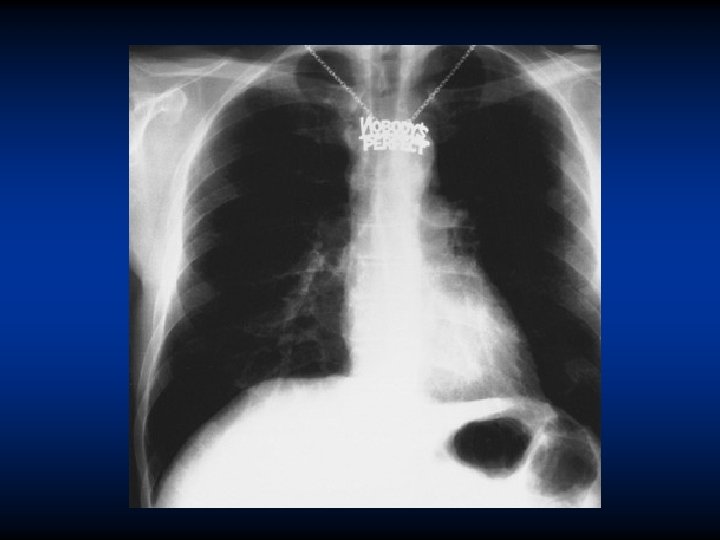

Srdeční stín • mitrální stenóza